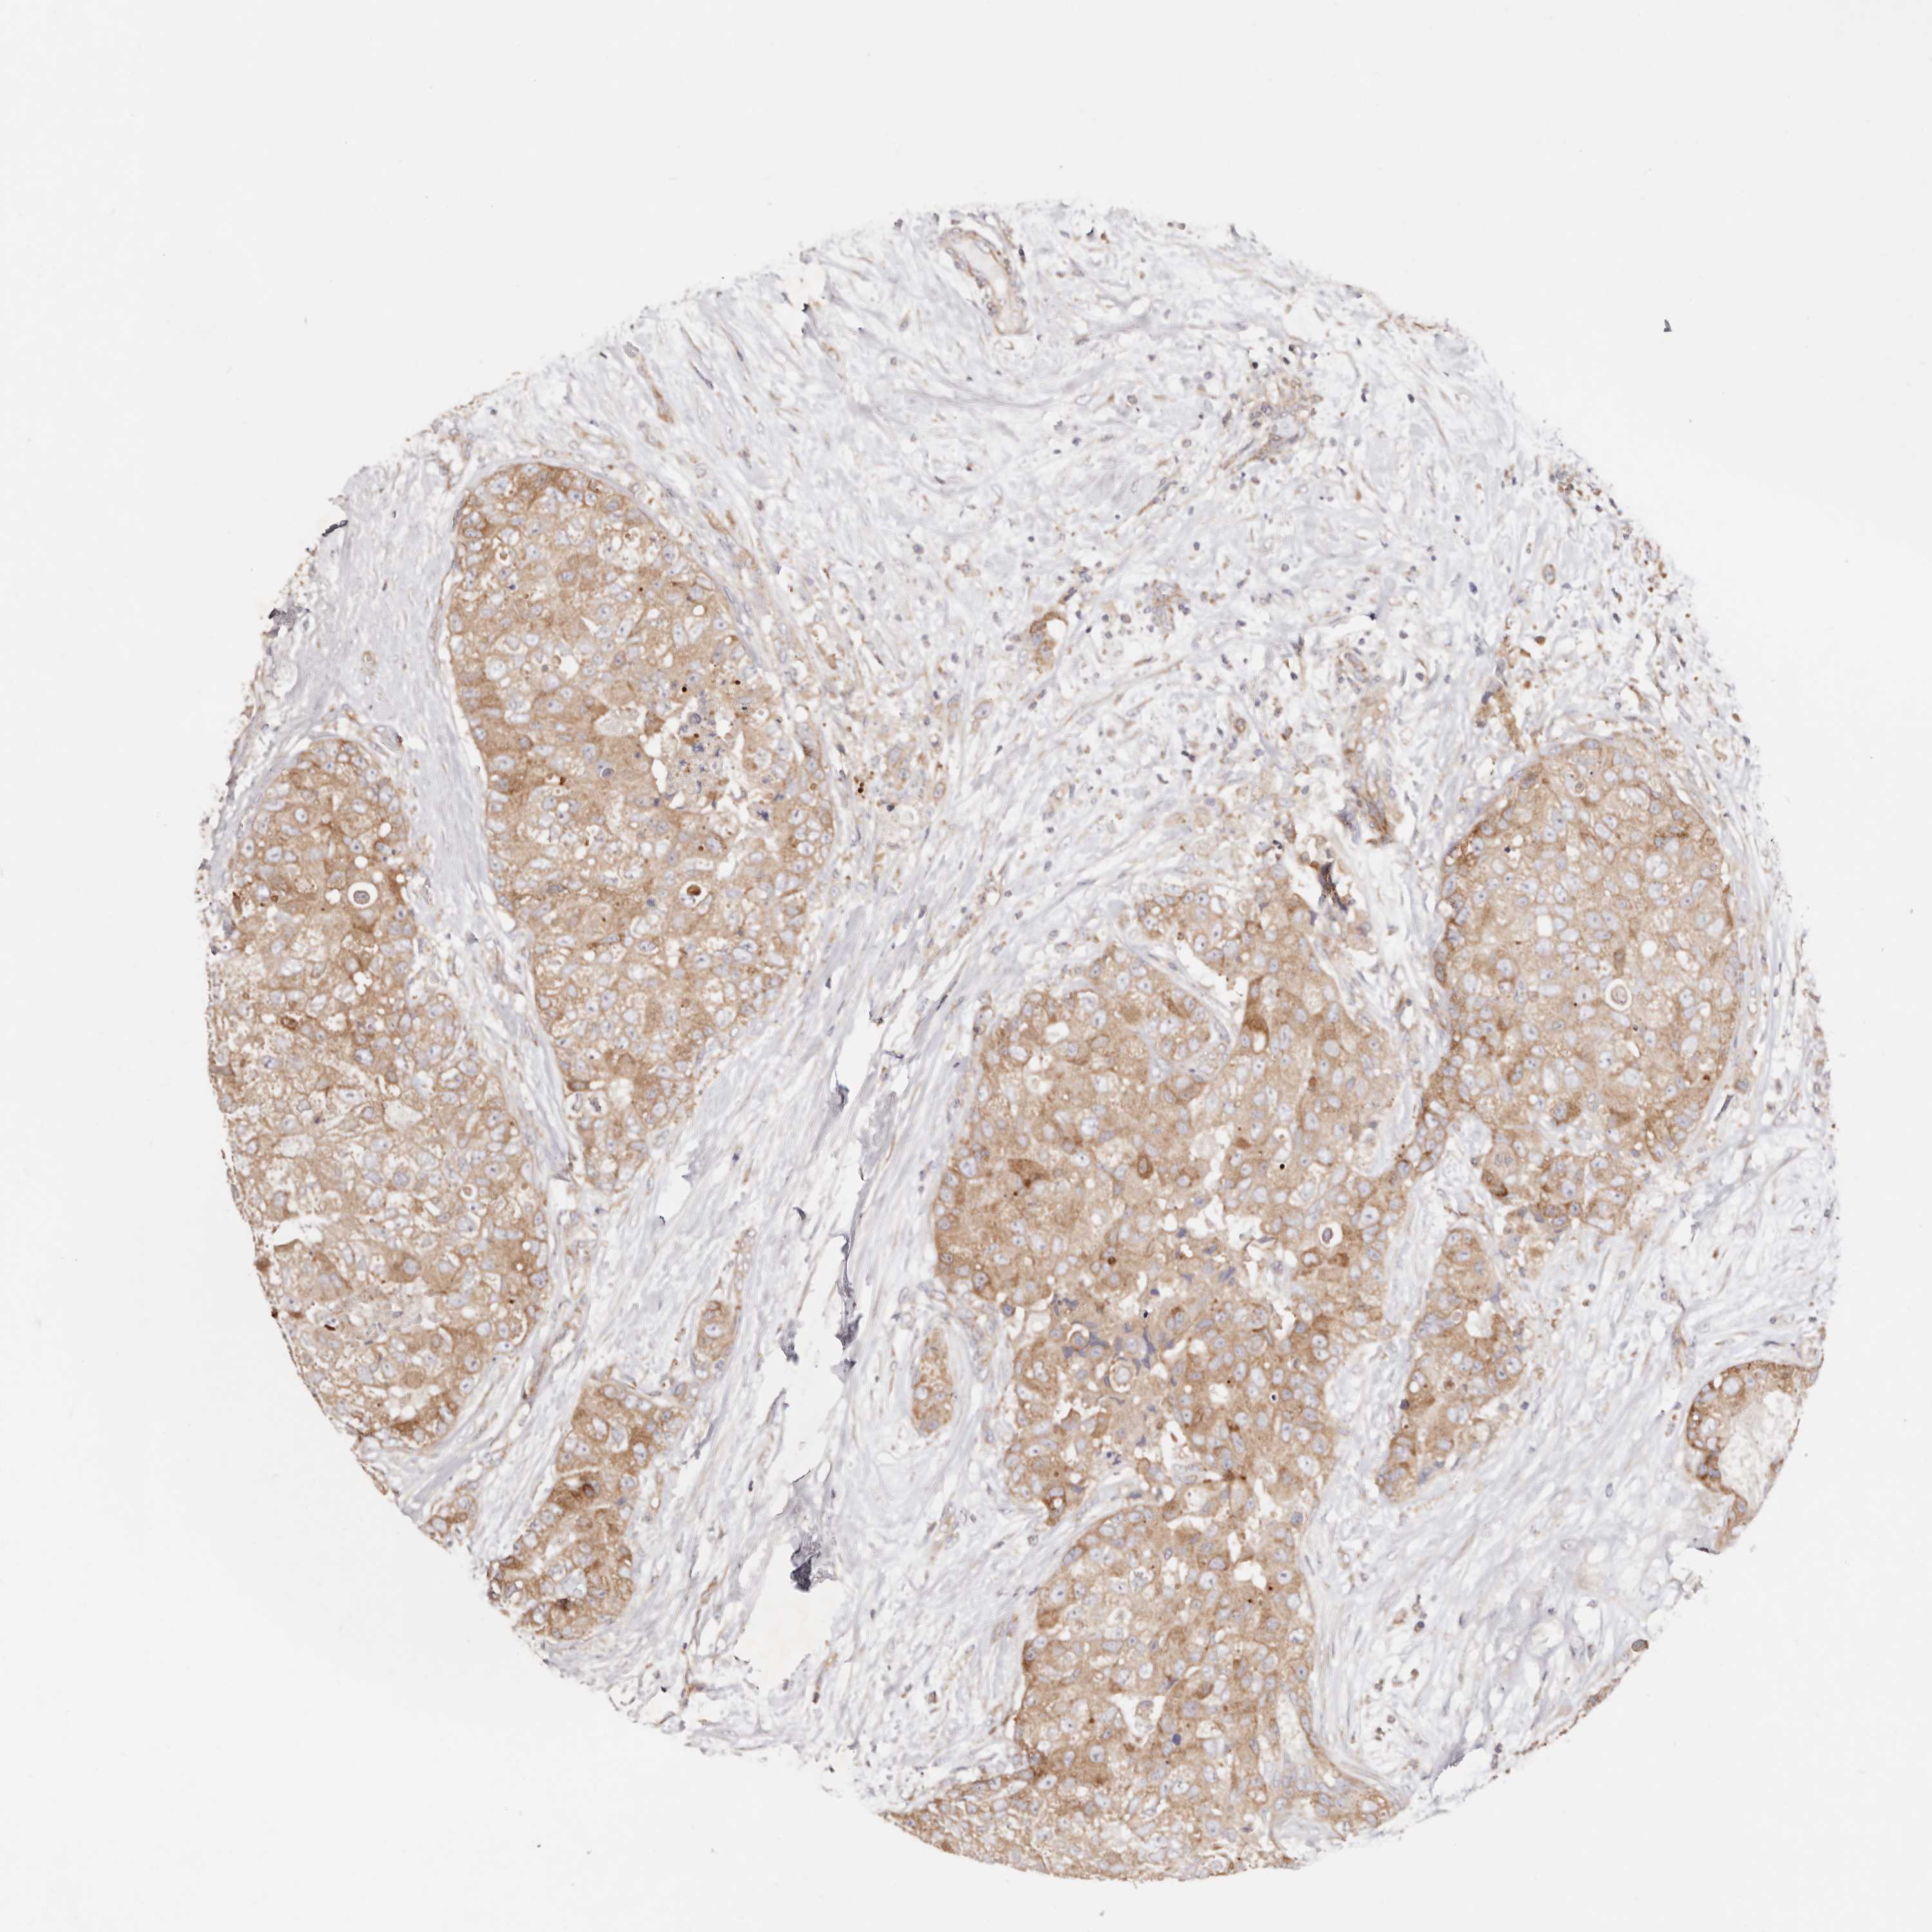

CANCER BREAST CANCER Show tissue menu

BRCA TCGA BRCA VALIDATION PROTEIN EXPRESSION